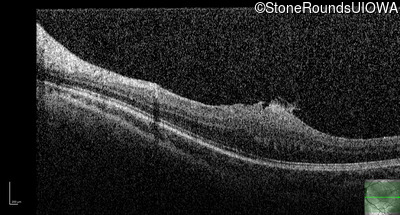

Optical Coherence Tomography - Left - 20/80

Exemplar / OCT Stack